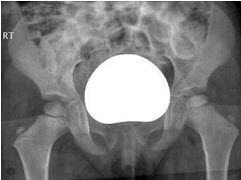

40、单项选择题  人体最重要的排泄器官是()

女,根据其正常骨盆影像图像,判断其最可能的年龄()

A.69岁左右

B.59岁左右

C.49岁左右

D.19岁左右

E.39岁左右

点击查看答案